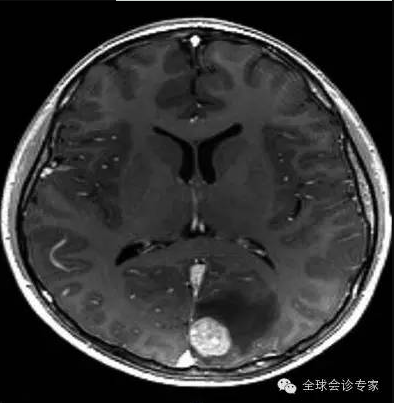

患者,65岁,男,2014年10月腹部不适、头疼检查,诊断为(1)高分化肝细胞癌,大小约250px,明显肝硬化。(2)脑转移瘤,左枕叶处大小约75px。(3)II型糖尿病,需要胰岛素治疗。(4)慢性肾病;(5)中度高血压,有心衰病史。

患者病情处于晚期,体内病灶巨大且有脑转移,不能实施外科手术治疗。经亨利福特医院专家组咨询,患者于2014年11月10日在美国亨利福特医院进行EDGE无创手术治疗。先后对肝脏肿瘤和脑转移瘤进行EDGE治疗,在医院共治疗8天。每个肿瘤每天治疗1次,每次治疗约10分钟左右,肝脏肿瘤共治疗6次,脑肿瘤治疗4次。

患者手术过程中无任何不适,每次治疗后正常回家。2015年5月回访,患者一般情况良好,体重明显增加。经影像检查,肝脏巨大肿瘤被彻底清除,脑部肿瘤几乎完全消除,且没有复发。生化检查,肝功能未见正常。

脑转转移瘤治疗前75px

脑转移瘤治疗后几乎完全消除